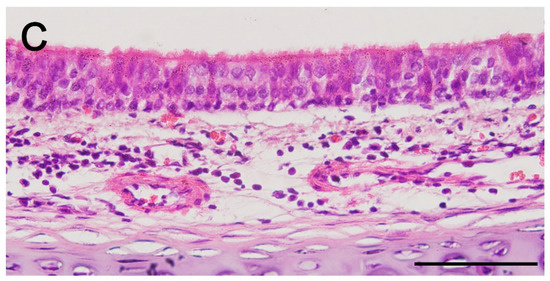

2.5. In Vivo Epithelialization and Neo-Cartilage Formation